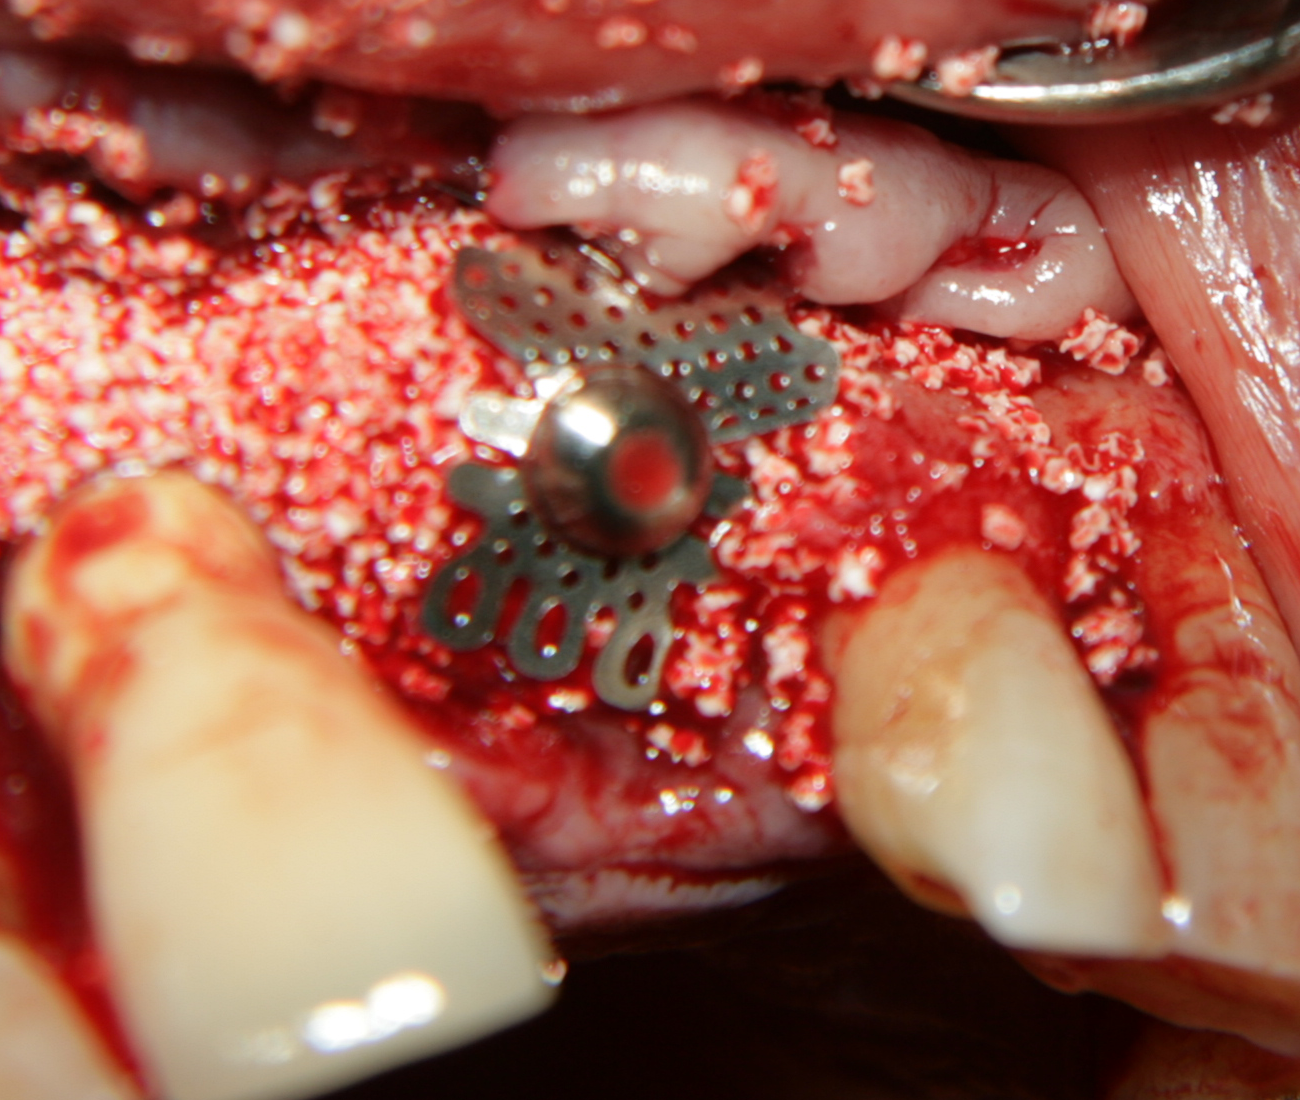

Аплициран е костозаместващ материал -

Kasios (Франция)

Костозаместителят е покрит с

титанова мрежа. Тя има полезен ефект - запазва формата на графта и

предпазва меките тъкани от колапс. По този начин се осигурява един стабилен

обем, който да се изпълни с костна тъкан. При липса на

титановата мрежа меките тъкани колабират, което е съпроводено със

значителна редукция на пространството за образуване на нова костна тъкан.

Важно е мрежата да бъде имобилизирана - всяка подвижност води до

костна резорбция на младата костна тъкан, съответно до опорочаване на

резултата от лечението.

Доскоро имобилизацията се осъществяваше с дебел конец, който захваща

свободния край на мрежата към вътрешната повърхност на периоста; от 2012

година обаче Neobiotech въведе т.нар.

GBR-kit, с помощта на който мрежите се фиксират с

различни по диаметър и дължина винтове.

Титановите мрежи дават много добър резултат при имедиатно поставяне на

зъбни

импланти след екстракция на зъби.